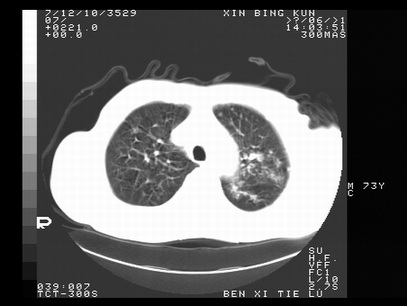

标题: CT10820:男,73岁,病史肺TB,现病史肺炎,直肠CA术后 [打印本页]

标题: CT10820:男,73岁,病史肺TB,现病史肺炎,直肠CA术后

双肺间质改变,依据病史双肺多发结节灶考虑转移,少量胸水.

1.两肺结核.2.两肺多发转移瘤.3右侧少量胸腔积液4.主动脉钙化.

双肺多发结节及条片状致密影,右侧少量胸腔积液。临床:直肠ca术后,肺tb病史。综合考虑:1 双肺转移!2 继发性肺结核合并感染!

此人病史较复杂,原有肺结核,直肠癌术后。肺部病灶形态亦呈多形性。因此,不可仅以一种病来解释肺部的病变。双肺多发的类圆形结节灶,结合病史还是首先考虑转移瘤,而双肺其余病灶还需结合化验室检查,结核或肺部感染在无其它检查资料的情况下不好排除。还是那句话----放射科医生不是开照像馆的,我们也是医生,看片一定要多结合临床及其它检查资料。要当一名合格的放射科医生,并不比当一名临床医生容易,我们可别把自已不当医生看。

两肺多发结节影,并见滋养动脉与其相连,考虑 两肺转移. 右侧胸腔积液考虑胸膜转移.

左肺上叶下叶背段,右肺中下叶见多发斑片状、条索状高密度影,兵变周围小结节影形成“树芽”样改变。 左肺上叶舌段近前胸壁处及右肺中叶内侧段见结节影。右侧胸膜腔内见液体密度区。纵隔内未见明确增大淋巴结。考虑左肺上叶舌段近前胸壁处及右肺中叶转移瘤可能性大。两肺继发型肺结核。右侧胸腔积液。